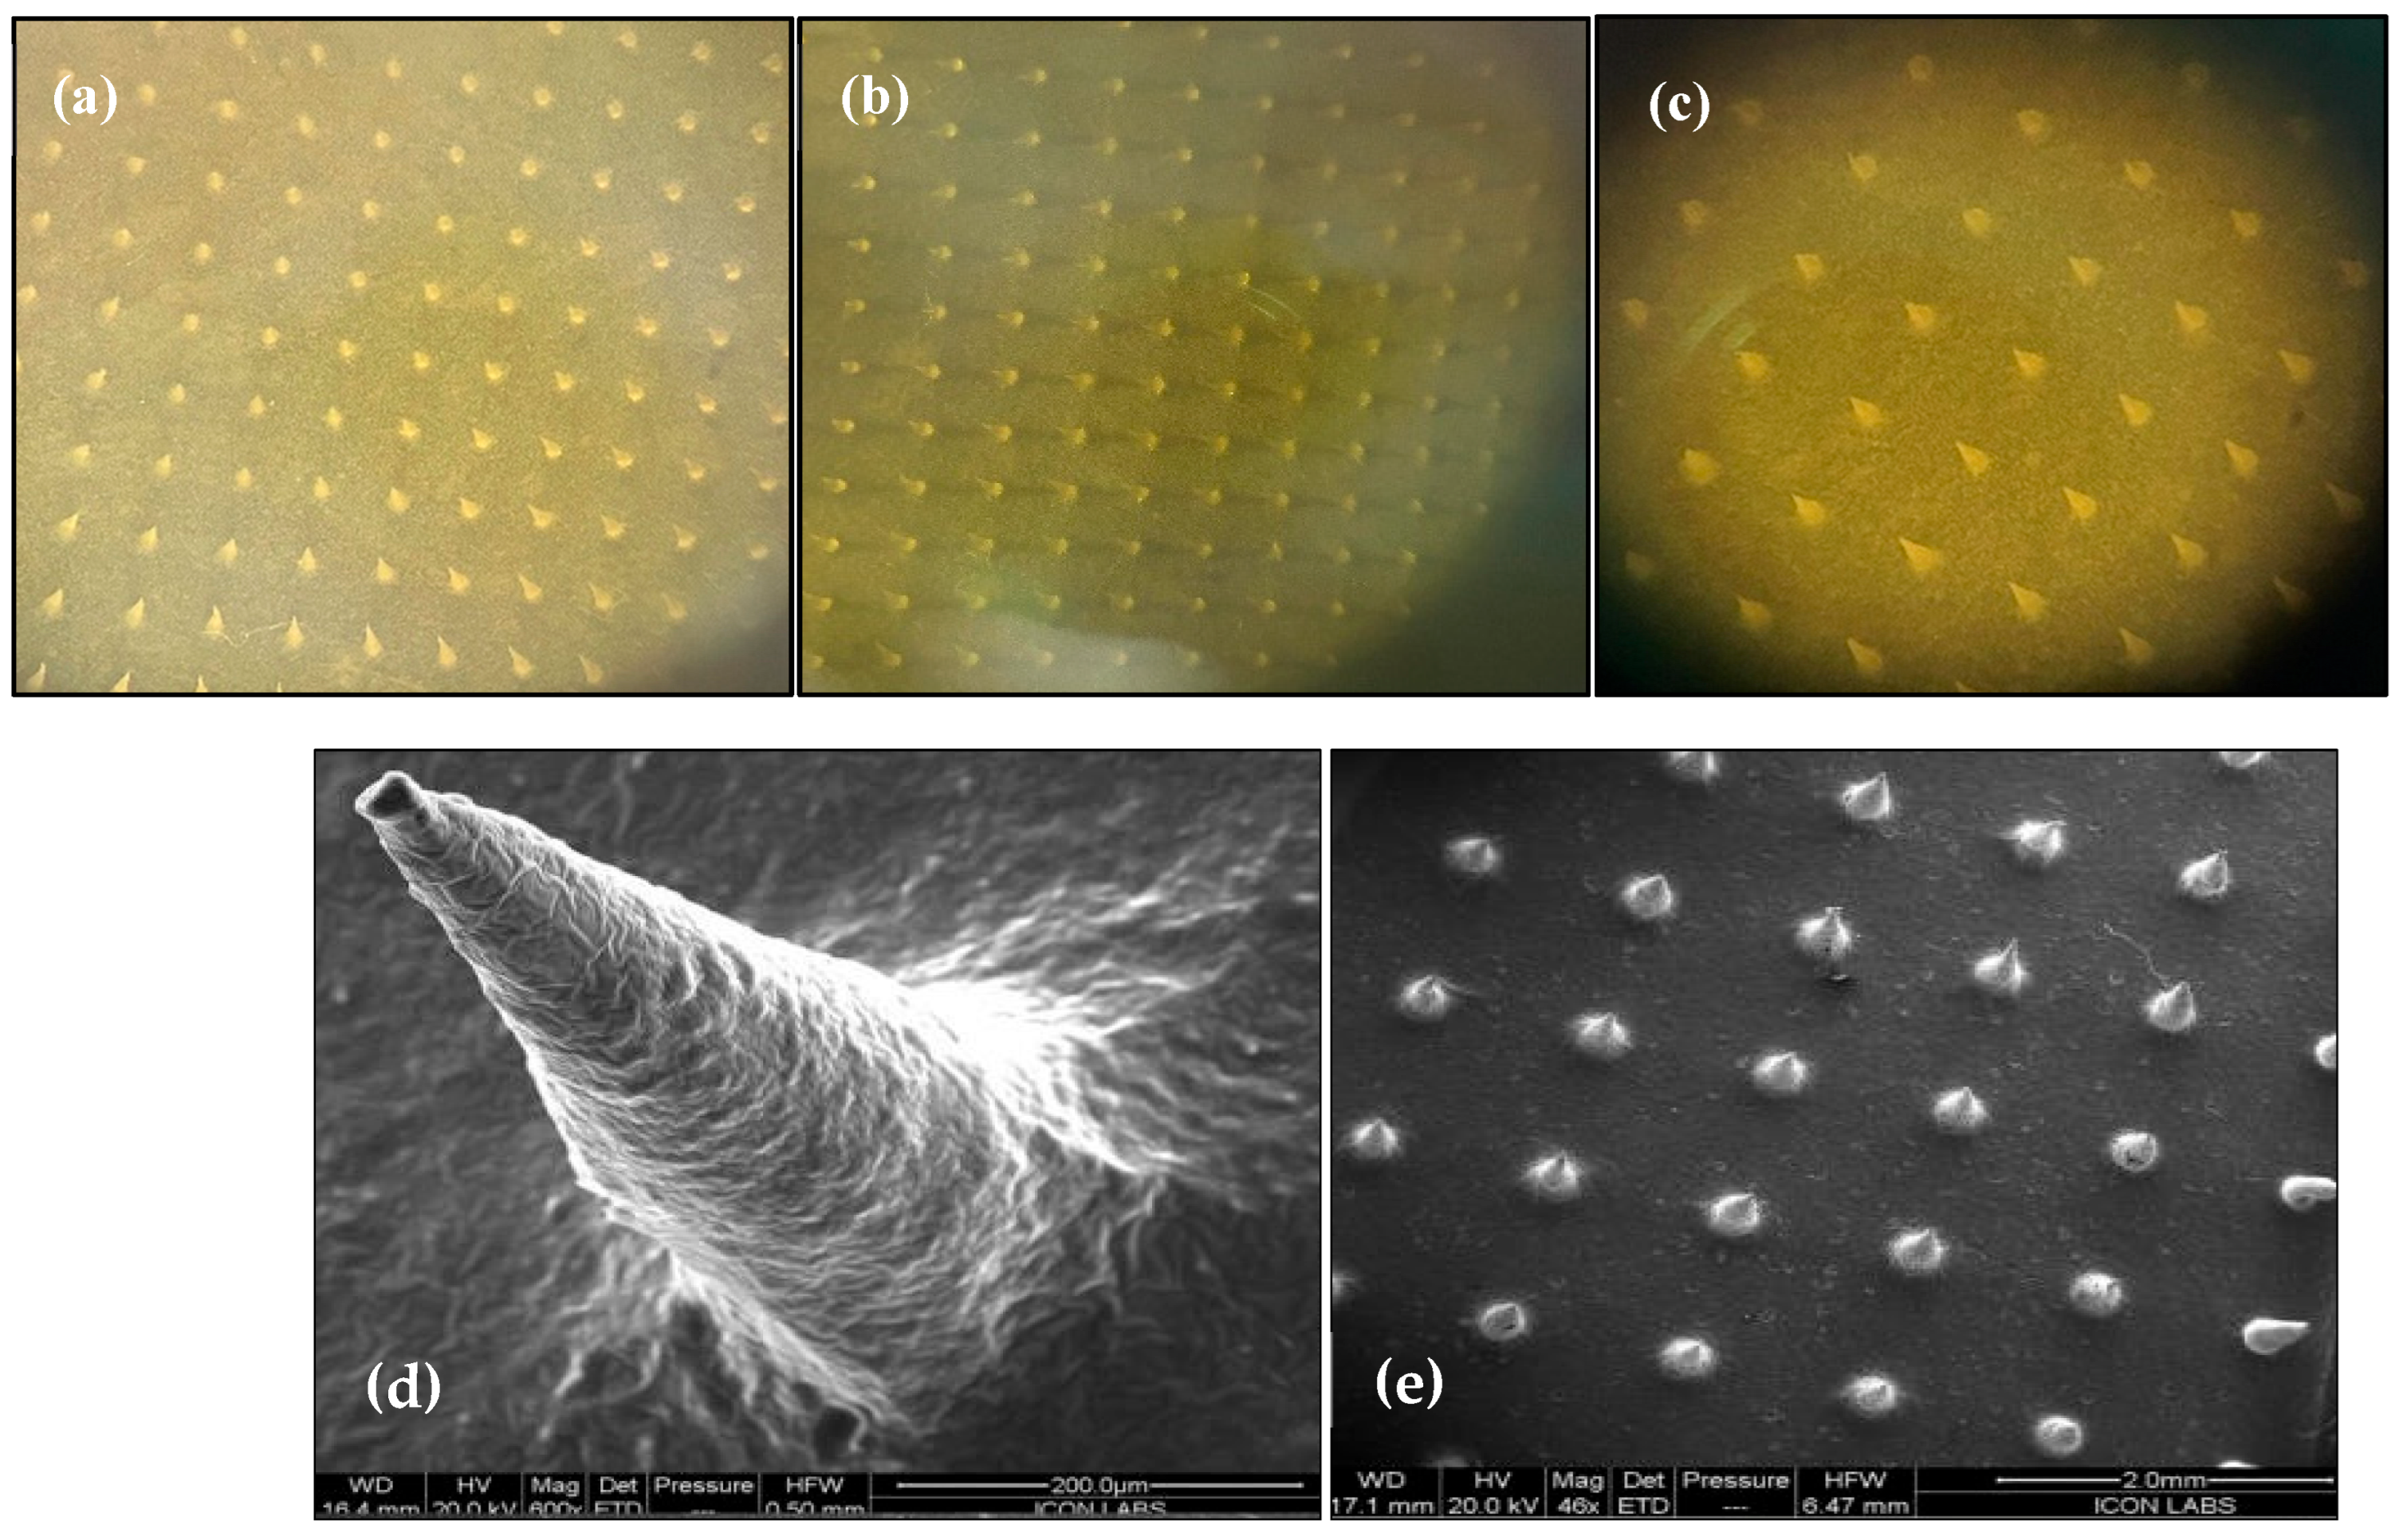

2.6. Fabrication and Morphological Characterization of MTX-MNs and MTX-TF-MNs

2.6.1. Characterization of Microneedle Array Patch

3.4. Morphological Characterization of MTX-TF-Loaded MNs

3.4.1. Optical Microscopy and Field Emission Scanning Electron Microscopy